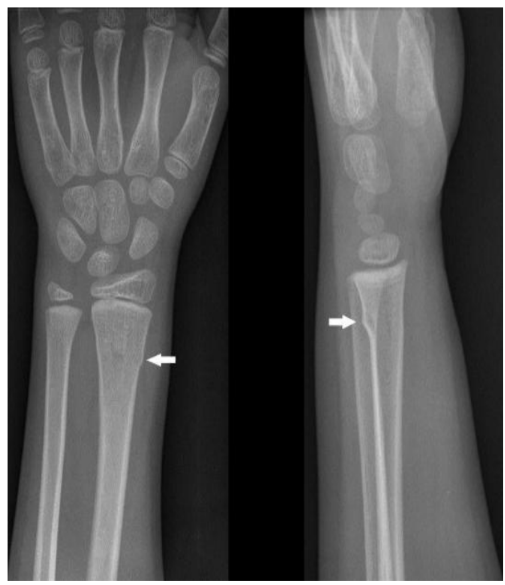

What is a buckle fracture of the radius (forearm)?

Your child has a break of one of the forearm bones near the wrist. Young bone is still soft and very flexible. As a result, instead of breaking all the way through, the bone has a small crack or kink to one side only.